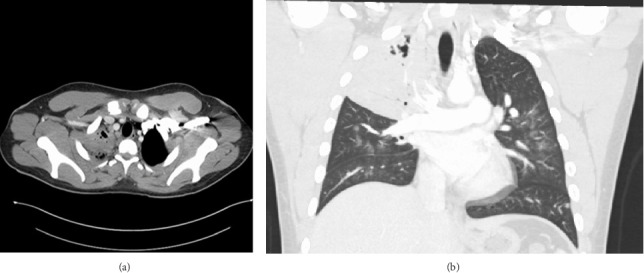

背景:电子烟的使用在年轻人中越来越普遍,这引起了人们对其潜在健康影响和感染易感性的担忧。枯草芽孢菌,芽孢菌病的病原体,是一种二态真菌地方性的某些地区的美国。我们报告了一例罕见的肺芽孢菌病,发生在一名长期使用电子烟的年轻免疫功能正常的男性患者身上,强调了在有呼吸道疾病危险因素的患者中,在鉴别诊断病因不明的肺炎时考虑真菌感染的必要性。症状:20岁男性,4年每日使用电子烟,职业为排水沟清洁工,10天咳嗽加重、痰血、呼吸短促、盗汗、发烧和体重减轻。他血流动力学稳定,需要最低限度的氧气支持,胸部x线片显示右上肺叶肺炎和空洞病变。患者接受了社区获得性肺炎、非典型肺炎、肉芽肿性疾病以及免疫抑制和病毒性淋巴细胞增生性疾病的检测。诊断性支气管镜检查最终确诊为芽菌病,并给予两性霉素B和伊曲康唑治疗,临床明显改善。结论:肺芽孢菌病多无症状表现,重症多见于老年人或有合并症和免疫功能障碍者。医生往往忽视它作为原发性肺部感染的鉴别诊断,关注年轻人的细菌性肺炎和结核病。这一案例强调了进一步调查电子烟使用对免疫功能影响的必要性。考虑到芽孢菌病的发病率不断上升,以及在整个州发生的广泛的建筑和土壤破坏,该病例还突出了使芽孢菌病成为格鲁吉亚一种可报告疾病的重要性。

Background: E-cigarette use has become increasingly prevalent among young adults, raising concerns about its potential health impact and susceptibility to infections. Blastomyces dematitidis, the causative agent of blastomycosis, is a dimorphic fungus endemic to certain regions of the United States. We present a rare presentation of pulmonary blastomycosis in a young, immunocompetent male with chronic e-cigarette use, highlighting the need to consider fungal infections in the differential diagnosis of pneumonia of unknown etiology in patients with risk factors for respiratory illness. Presentation: A 20-year-old male with a 4-year history of daily e-cigarette use and gutter cleaner by occupation presented with a 10-day history of worsening cough, bloody sputum, shortness of breath, night sweats, fever, and weight loss. He was hemodynamically stable, required minimal oxygen support, and was admitted for chest X-ray showing right upper lobe pneumonia and cavitary lesion. The patient was tested for community-acquired pneumonia, atypical pneumonia, granulomatous diseases, and immunosuppressive and viral lymphoproliferative disorders. A diagnostic bronchoscopy ultimately confirmed blastomycosis, leading to treatment with amphotericin B and itraconazole, resulting in significant clinical improvement. Conclusion: Pulmonary blastomycosis often presents asymptomatically, with severe cases more common in the elderly or those with comorbidities and immune dysfunction. Physicians tend to overlook it as a differential diagnosis for primary lung infections, focusing on bacterial pneumonia and tuberculosis in younger individuals. This case underscores the need for further investigation into the impact of e-cigarette use on immune function. This case also highlights the importance of making blastomycosis a reportable disease in Georgia, considering its increasing incidence and the widespread construction and soil disturbance occurring throughout the state.